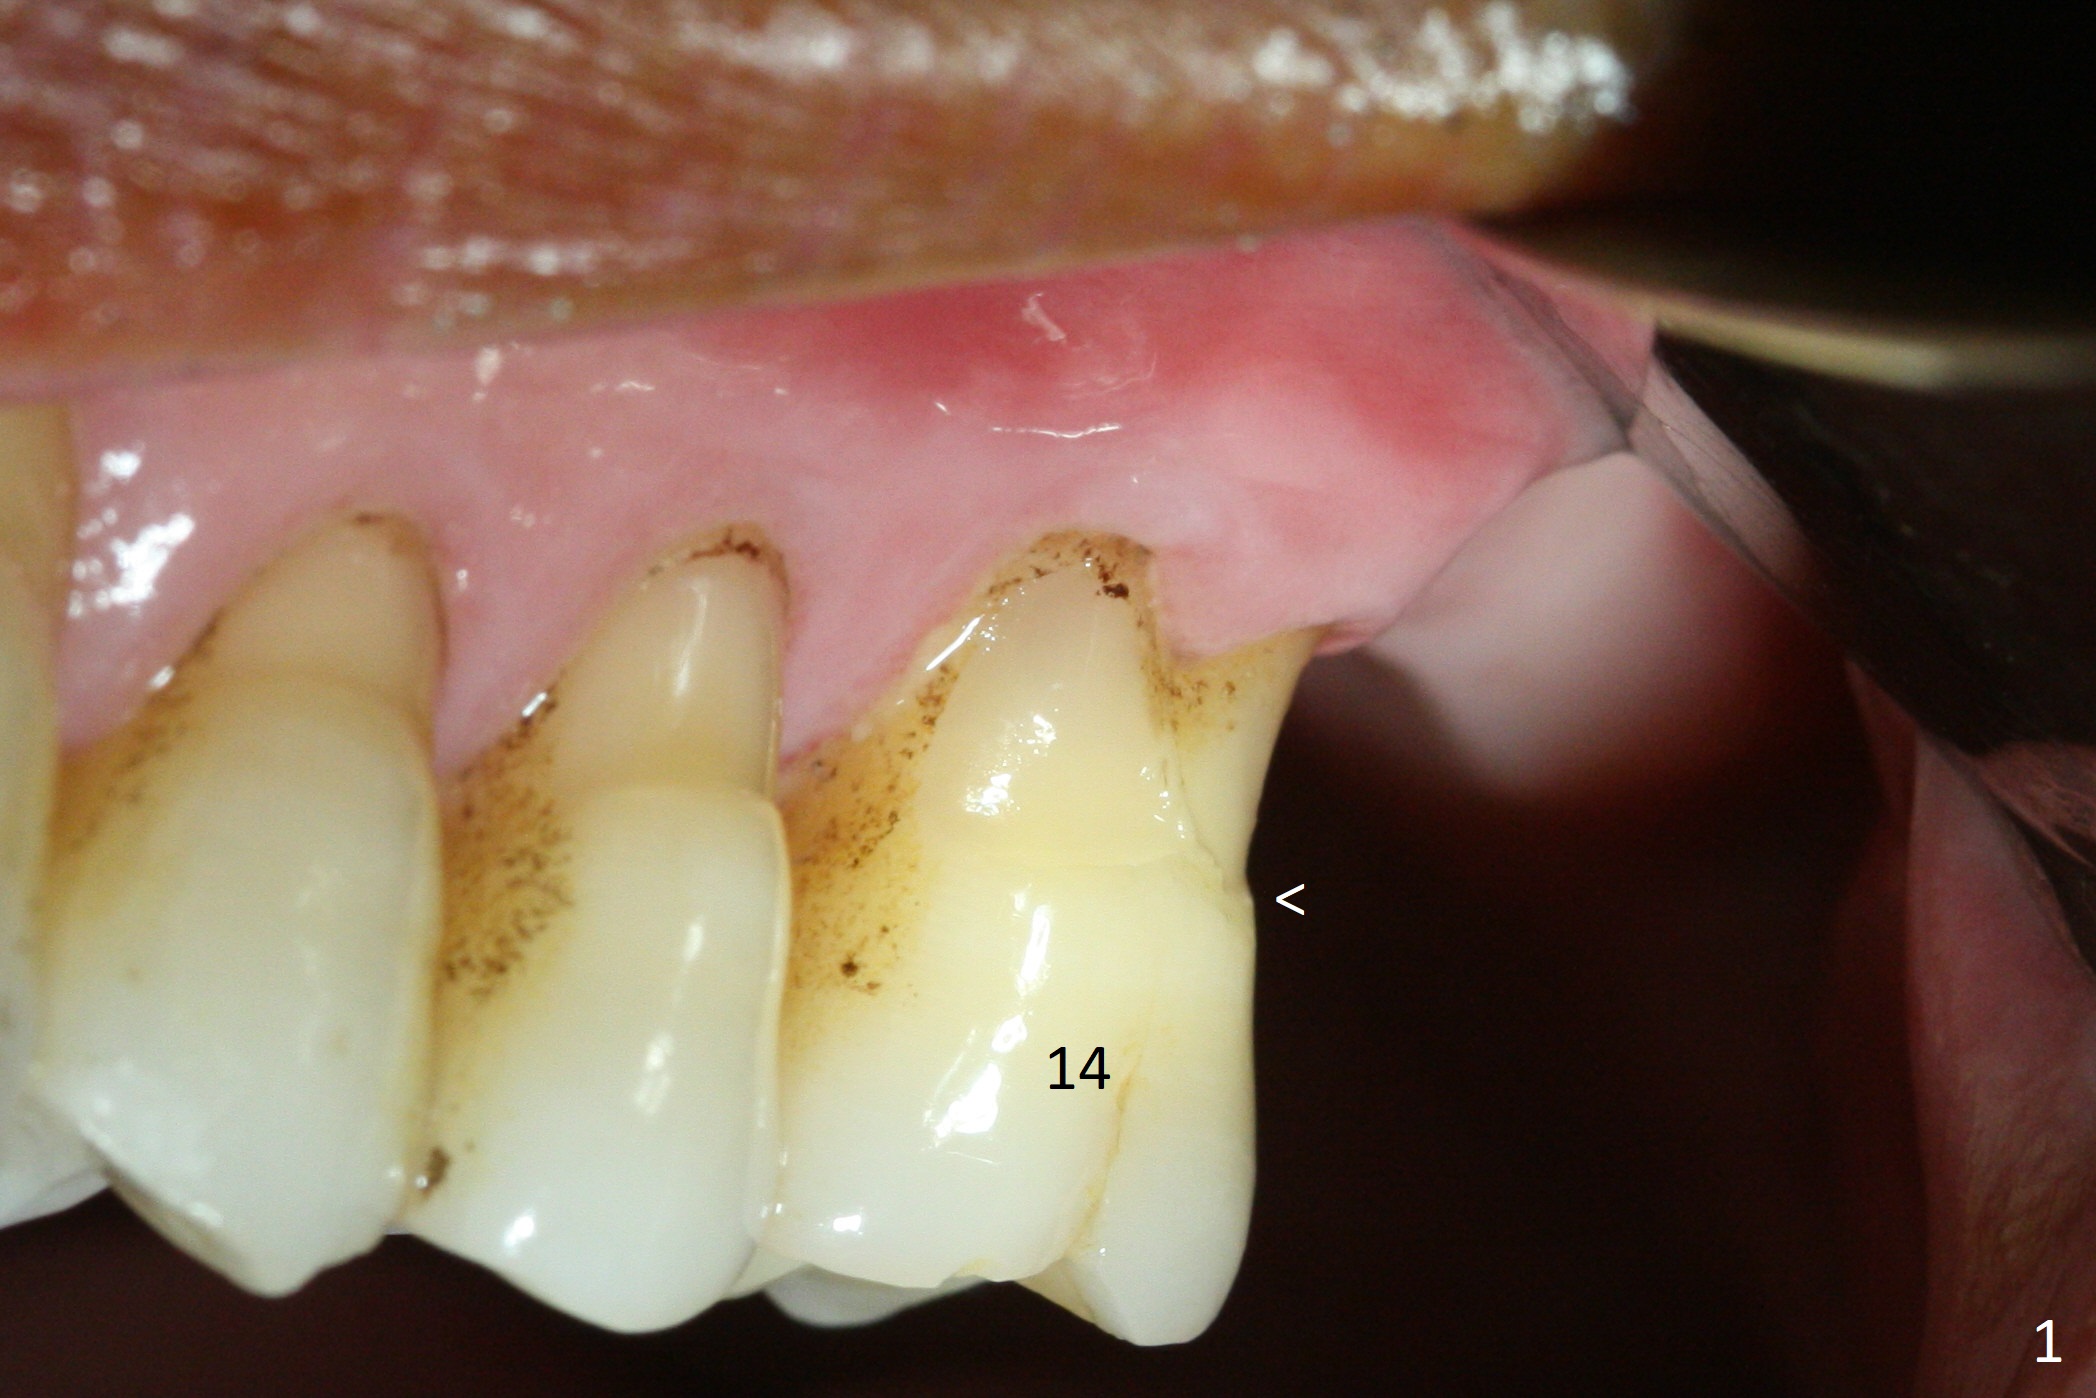

Buccal gingival recession at #14 (Fig.1) is less severe than the palatal one (Fig.2). Without raising the buccal gingiva (Fig.3 B), osteotomy in the septum is established apparently in the middle socket (Fig.3 *, 4). As the osteotomy increases with 3.8 mm drill, the palatal wall of the osteotomy starts to be perforating. When a 4.5x11.5 mm implant is placed, palatal threads are exposed, to which autogenous bone and Vera Graft are placed (Fig.5 *). After placement of a 5.5x5(3) mm abutment, an immediate provisional (Fig.6 P) is fabricated to cover the sockets. If the septal dimension were studied carefully by raising the buccal gingiva slightly, the osteotomy could be initially more buccal so that the palatal thread exposure could be less. When the provisional is removed 1.5 months postop, the implant is exposed palatally. The margin of the provisional is modified so that the implant can be cleaned by the patient using Water Pik. In fact, the healthy gingiva seems to be attached to the implant threads 2 weeks later (Fig.7). The distal implant threads remains exposed 6 months postop; it appears that the distal socket wall has resorbed (Fig.8). The sockets heal 1 year 7 months post cementation (Fig.9).